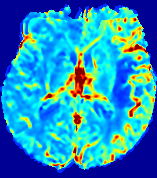

LesionRefer to captionRefer to captionRefer to captionRefer to captionRefer to captionRefer to caption𝐕rgbsubscript𝐕𝑟𝑔𝑏{\bf{V}}_{rgb}Refer to captionRefer to captionRefer to captionRefer to captionRefer to captionRefer to caption𝐕2subscriptnorm𝐕2{\|\bf{V}}\|_{2}Refer to captionRefer to captionRefer to captionRefer to captionRefer to captionRefer to captionRefer to caption3.53.53.52.82.82.82.12.12.11.41.41.40.70.70.70.00.00.0(mm/s)𝑚𝑚𝑠(mm/s)D𝐷DRefer to captionRefer to captionRefer to captionRefer to captionRefer to captionRefer to captionRefer to caption0.0200.0200.0200.0160.0160.0160.0120.0120.0120.0080.0080.0080.0040.0040.0040.0000.0000.000(mm2/s)𝑚superscript𝑚2𝑠(mm^{2}/s)Slice #1Slice #2Slice #3Slice #4Slice #5Slice #6

Figure 3: PIANO feature maps for one stroke patient, where the lesion is located in the left hemisphere. Top row: segmented stroke lesion region (white) on different slices, obtained from ISLES 2017. The corresponding slices for the PIANO feature maps are shown in the following rows.

For a better insight into an estimated velocity field 𝐕𝐕{\bf{V}} and diffusion field 𝐃𝐃{\bf{D}}, we compute the following maps: (1) 𝐕rgbsubscript𝐕𝑟𝑔𝑏{\bf{V}}_{rgb}: Color-coded orientation map of 𝐕=(Vx,Vy,Vz)T𝐕superscriptsuperscript𝑉𝑥superscript𝑉𝑦superscript𝑉𝑧𝑇{\bf{V}}=(V^{x},V^{y},V^{z})^{T}, obtained by normalizing 𝐕𝐕{\bf{V}} to unit length and mapping its 3 components to red, green, blue respectively; (2) 𝐕2subscriptnorm𝐕2\|{\bf{V}}\|_{2}: 222 norm of 𝐕𝐕{\bf{V}}; (3) D𝐷D: scalar field in Eq. 5.

Fig. 3 and Fig. 4 show the PIANO feature maps estimated from two ISLES 2017 patients: all are highly consistent with the lesion in both cases. Details of the blood flow trajectories are revealed in 𝐕rgbsubscript𝐕𝑟𝑔𝑏{\bf{V}}_{rgb} by the ridged patterns and the sharp changes of colors in the unaffected (right) hemisphere, while the flat patterns appearing within the lesion provide little directional information about the velocity and indicate low velocity magnitudes. Velocity magnitudes are more directly visualized via 𝐕2subscriptnorm𝐕2\|{\bf{V}}\|_{2}, from which one can easily locate the lesion where 𝐕2subscriptnorm𝐕2\|{\bf{V}}\|_{2} is low. D𝐷D also indicates lower diffusion values in the lesion, though with less contrast potentially due to the fact that it captures the accumulated effect of CA diffusion at the voxel-level.